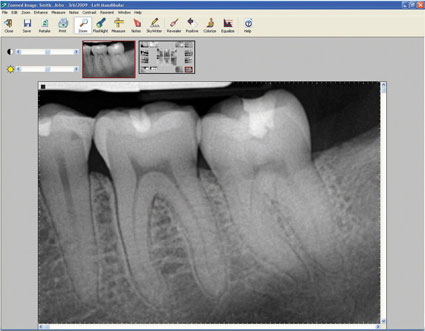

We are dealers for Sopro Imaging and can supply the popular PSPIX and Digora Optime Scanners fully integrated to the Shire Dental System.

Smart design, ergonomics and compact with a consistent image quality, PSPIX, the new Digital Imaging Plate System is designed to make intra oral imaging in the dental office easier and more efficient.

Four sizes of Imaging plates, thin and flexible with an active area optimized to 100%.

With PSPIX, the readout process of 4.3 sec. is completely automatic and a screen allows you to control the different steps of the process and to view your shot.

Fully Integrated to the Shire Dental System allowing images to be viewed on any woorkstation.

We can also supply the Durr Vista Scan for interoral and OPG scanning.

We are happy to link to any other type of digital x-ray, inter-oral camera and digital photographs.

We have developed sophisticated links to Image handling software such as the Schick Technologies CDR Dicom for Windows, Sopro, Kodak Trophy, Dexis, Owandy QuickVision & Gendex.